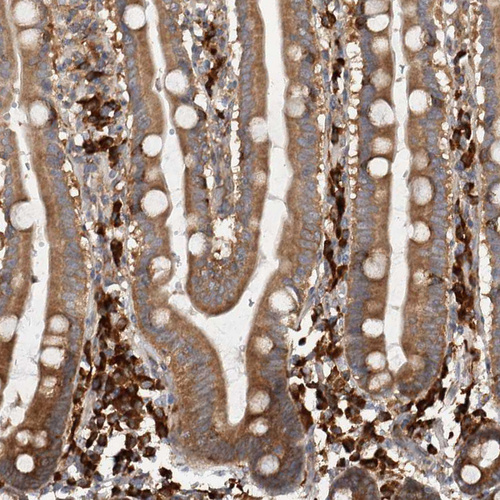

Immunohistochemical staining of human duodenum shows strong cytoplasmic positivity in lymphoid cells.